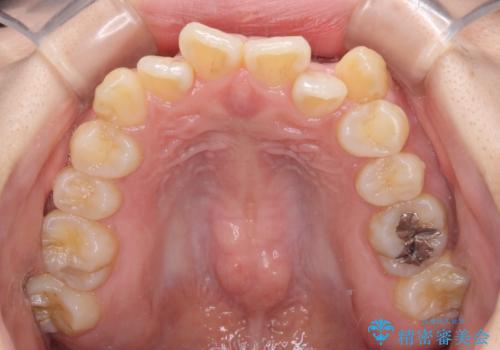

- 八重歯や前歯の捻転とクロスバイトが気になり、インビザラインによる矯正治療を希望して来院された患者様です。

上顎側切歯(上の真ん中から2番目の歯)が舌側転位している場合、無理して動かそうとすると歯髄壊死を起こすリスクが高い印象があります。

インビザライン単体でも治療は可能ですが、安全策としてインビザラインで歯列を移動する前に上顎前歯をワイヤー矯正で整え、その後上下歯列をインビザラインにて矯正治療を行うこととしました。

舌側転位している側切歯特有の、切縁の位置が不揃いであったり、根元が内側に引っ込んだ状態であったりという、インビザライン独特の仕上がりになることなく、きれいに整った歯列とすることができました。